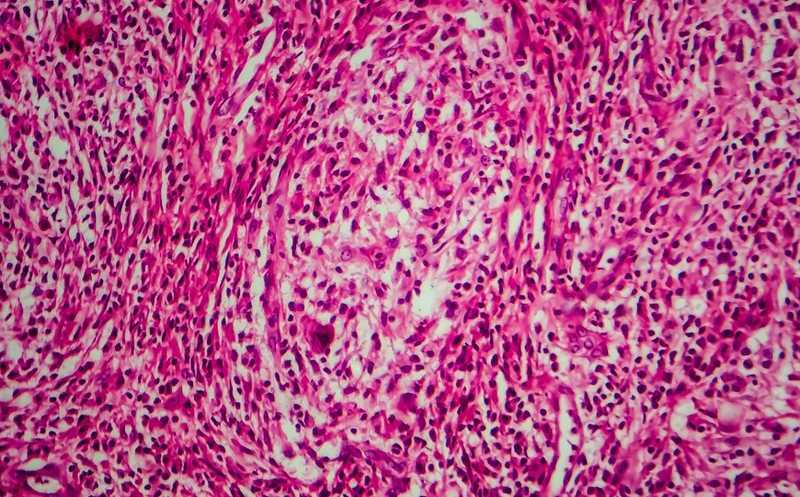

Выявленные подтипы фолликулярной лимфомы и их характеристики.Credit:

Cell Reports Medicine (2025). DOI: 10.1016/j.xcrm.2025.102278 | CC BY

ФЛ подтипов C1 и C3 имели более злокачественную (high-grade) морфологию по данным гистологического исследования. При этом у пациентов с C1-опухолями были выше показатели выживаемости без прогрессии и ниже риск ранней прогрессии заболевания, а при C3-подтипе — наоборот. Опухоли из группы C2 были ассоциированы с менее злокачественной (low-grade) морфологией, низким риском ранней прогрессии и промежуточными показателями выживаемости без прогрессирования.